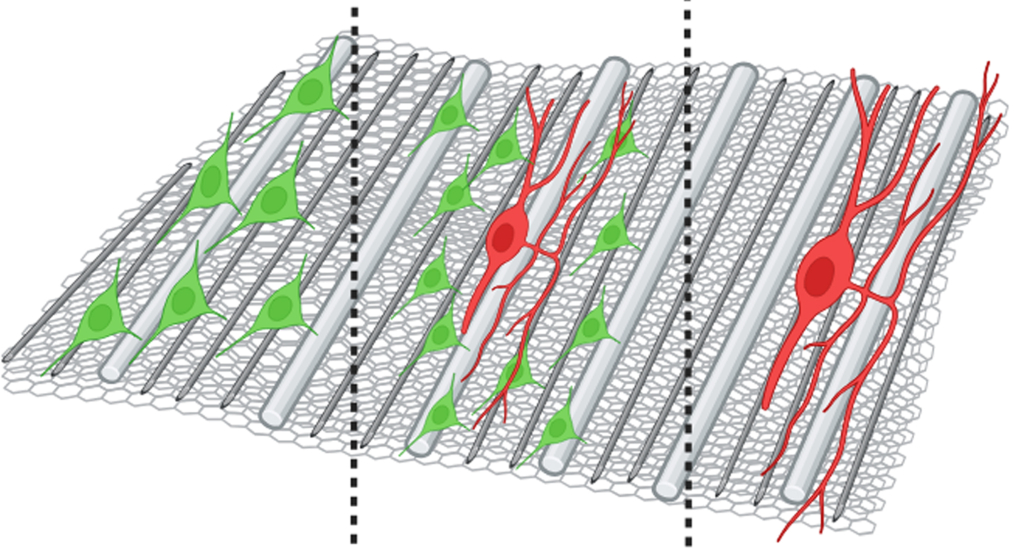

Ультраструктура композитного наноматериала способствует пролиферации шванновских клеток (зелёные) а также направляет рост аксонов (красные)

Ультраструктура композитного наноматериала способствует пролиферации шванновских клеток (зелёные) а также направляет рост аксонов (красные)

Учёные ИТЭБ РАН синтезировали ряд многослойных волокнистых наноматериалов и изучили влияние взаимного расположения слоёв и диаметра волокон на рост шванновских клеток (ШК), являющихся важным элементом нейроглии (совокупности вспомогательных клеток нервной ткани).

Исследование прокомментировала старший научный сотрудник лаборатории исследований генома кандидат биологических наук Ольга Антонова: «ШК играют особенно важную роль в процессах регенерации после повреждения нерва — они формируют так называемые ленты Бюнгнера, служащие направляющими структурами для роста новых аксонов в процессе восстановления нервного волокна. В данной работе, используя технологию послойного электроспиннинга, мы получили материалы (скаффолды), состоящие из высокоориентированных полимерных микро- и нановолокон, и показали, что они способствуют пролиферации и росту, а также значительному удлинению отростков ШК и формированию полосовидных структур, подобных лентам Бюнгнера, которые стимулируют рост аксонов in vitro.

Наилучшие результаты продемонстрировали скаффолды из композитного двухслойного наноматериала, состоящего из слоёв волокон с диаметрами 60 нм и 200 нм. Подложки из такого материала с предварительно выращенными ШК при контакте с органоидами спинного мозга (дорзальными корешковыми ганглиями) значительно ускоряют рост аксонов спинномозговых нервов в модели ex vivo».